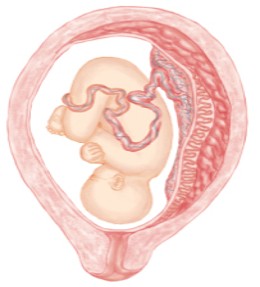

The premature separation of the placenta from the uterine wall before birth, potentially leading to bleeding and hematoma formation on the maternal side of the placenta.

Blood Flows out

Hematoma